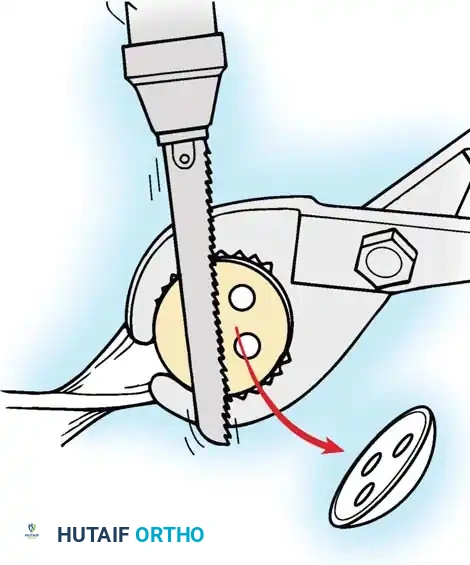

Removing the Tibial Component

With all-polyethylene tibial components, the interface can be disrupted using an oscillating saw to cut directly through the polyethylene stem, allowing access to the bone-cement interface.

Fig. 6-80A Disruption of the polyethylene interface using an oscillating saw.

For metal-backed tibial components, freeing the undersurface of the baseplate with thin osteotomes or a Gigli saw usually allows extraction.

Fig. 6-80B Accessing the bone-cement interface of a metal-backed component.

If the stem is long, fully cemented, or features a porous ingrowth surface, a long tibial tubercle osteotomy may be required to safely disimpact the keel without fracturing the proximal tibia.